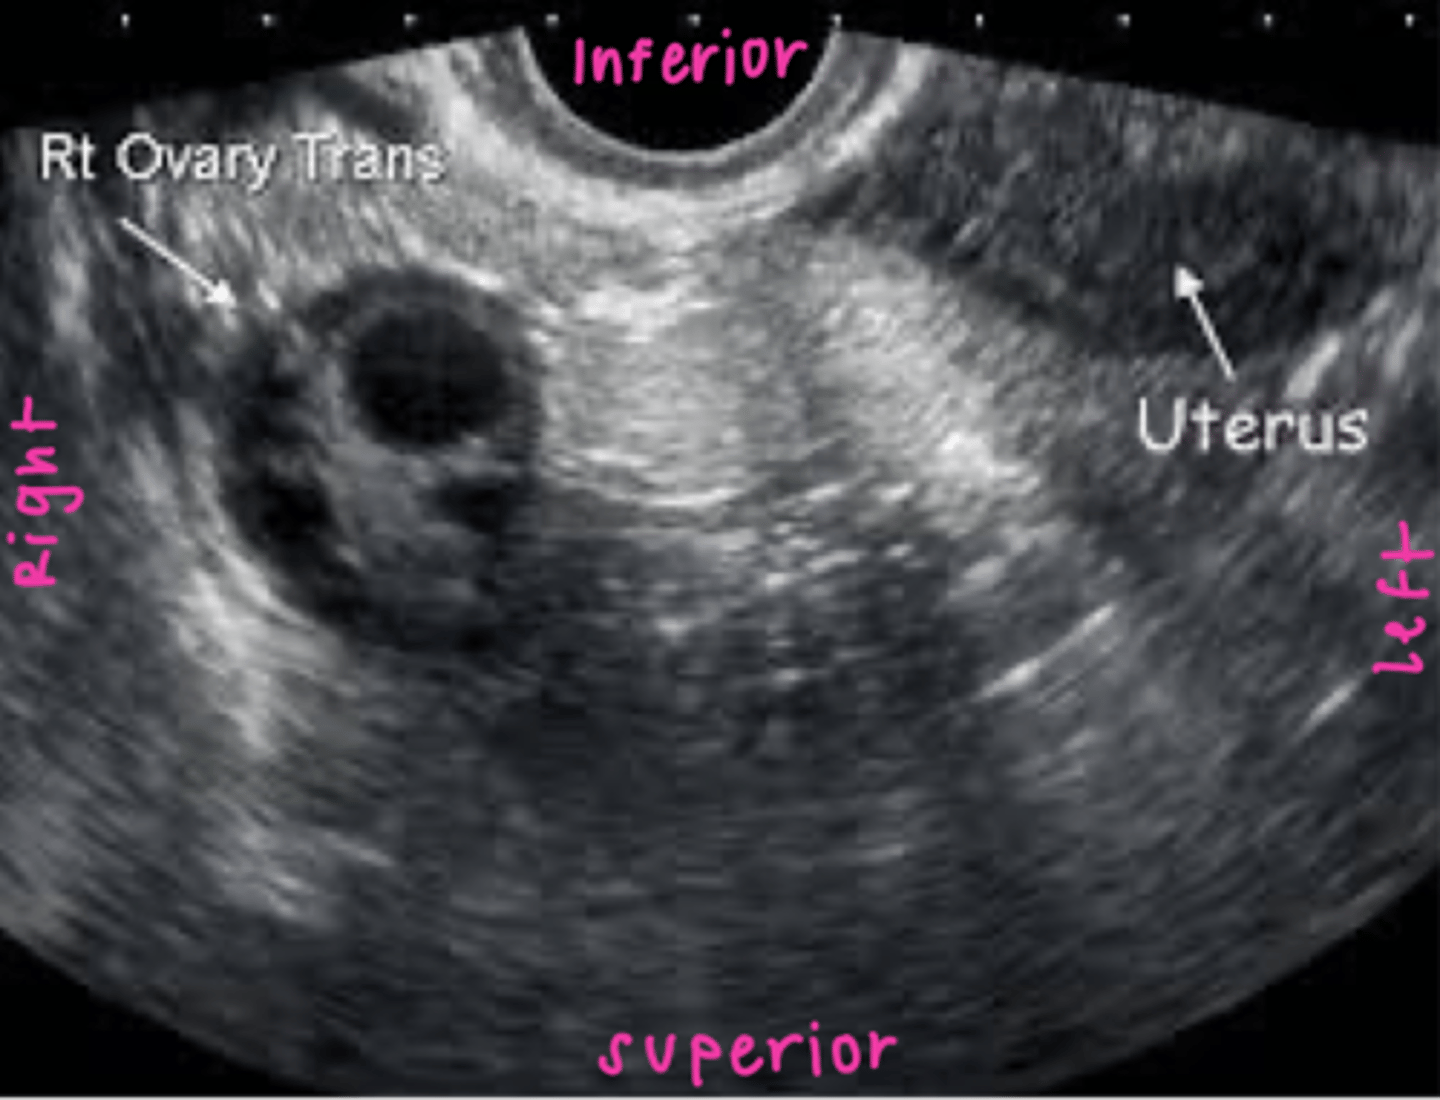

Ovaries are located in the ___ within the ___

adnexa; true pelvis

Ovaries are ___ to the internal iliac arteries and ___ to ureters

medial; anterior

Ovary size varies depending on patient:

age

menstrual cycle phase / status

TV sagittal image orientation

TV coronal image orientation